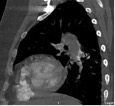

В статье представлен случай успешного хирургического лечения тромбоэмболии легочной артерии у пациентки с высоким риском ранней сердечной смерти на фоне парадоксальной эмболии, осложненной острым нарушением мозгового кровообращения. Криптогенное острое нарушение мозгового кровообращения в комбинации с тяжелой прогрессирующей правожелудочковой недостаточностью на фоне ТЭЛА обусловливает серьезные трудности при принятии решения в отношении тактики лечения у данных больных. Внутрисердечная локализация тромбоэмбола, угрожаемая развитием не только рецидива тромбоэмболии легочной артерии, но и парадоксальной эмболии требует незамедлительного выполнения комплекса дифференциально-диагностического обследования, направленного на верификацию патофизиологического механизма развития заболевания, что во многом определяет эффективность проводимого лечения. Анализ доступных литературных данных, приведенный в работе, а также анализ клинического случая позволяют выработать тактический алгоритм в этой группе пациентов и определить показания к открытому оперативному вмешательству.

Гамзаев А.Б., Федоров С.А., Чигинев В.А., Пичугин В.В., Теплицкая В.В., Сухова М.Б., Пименова П.В., Домнин С.Е. Хирургическое лечение тромбоэмболии легочной артерии высокого риска на фоне парадоксальной эмболии, осложненной острым нарушением мозгового кровообращения. Вестник хирургии имени И.И. Грекова. 2022;181(3):69-75. https://doi.org/10.24884/0042-4625-2022-181-3-69-75

Gamzaev A.B., Fedorov S.A., Chiginev V.A., Pichugin V.V., Teplitskaya V.V., Sukhova M.B., Pimenova P.V., Domnin S.E. Surgical treatment of high-risk pulmonary embolism associated with paradoxical embolism, complicated by acute cerebrovascular accident. Grekov's Bulletin of Surgery. 2022;181(3):69-75. (In Russ.) https://doi.org/10.24884/0042-4625-2022-181-3-69-75